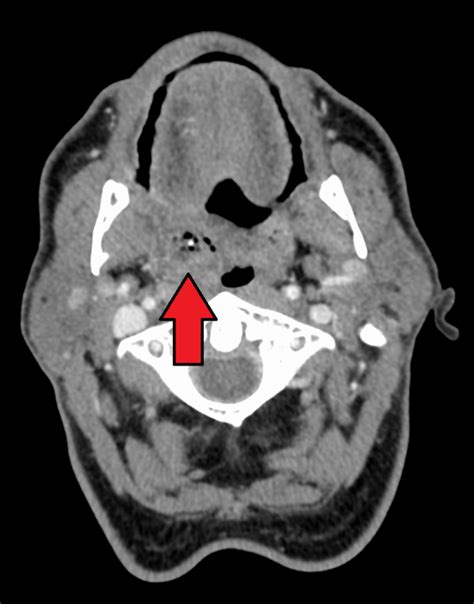

From a medical journal perspective, PTAs are polymicrobial infections, meaning they involve a mix of different bacteria. The usual suspects include Streptococcus pyogenes (the same bacteria that causes strep throat), Staphylococcus aureus , and various anaerobic bacteria. These little buggers team up to cause inflammation and pus formation, leading to that painful abscess. Diagnosing a PTA typically involves a physical exam, where a doctor will look for swelling and redness around the tonsils. They might also feel for a fluctuant mass, which is a fancy way of saying a squishy, pus-filled lump. In some cases, imaging tests like a CT scan might be necessary to confirm the diagnosis and rule out other issues.

• Imaging Tests: In some cases, imaging tests like a CT scan may be necessary. This is especially true if the diagnosis is unclear or if there are concerns about the infection spreading.